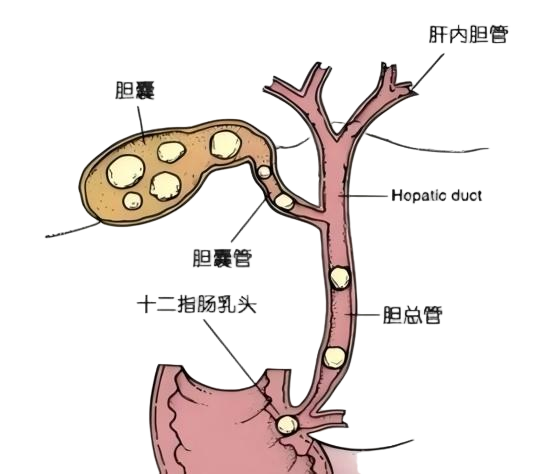

谁能想到,让杨先生陷入“生死劫”的竟是胆囊和胆总管里的两颗结石。

后背撕裂般的疼痛、整夜无法入睡……这些年来,这两处“定时炸弹”一次次将杨先生推向痛苦的深渊。更让他揪心的是,多家医院给出的方案几乎一致:开刀切胆囊,做ERCP取石。两次手术,双重煎熬,杨先生一度陷入绝望。

又一次打起精神,杨先生来到西京医院九八六医院消化内科就诊。检查发现,他的总胆红素已经飙升到163.31μmol/L,远超正常参考范围,而且胆囊、胆总管末端均有结石,若不及时处理,可能引发急性胆管炎、梗阻性化脓性胆管炎、肝功能严重受损甚至胰腺炎等危及生命的并发症。

就在他以为难逃“两刀”命运时,消化内科王钧主任团队提出了一个让他惊喜的方案:一次ERCP微创手术,同时解决两处结石,还能保住胆囊!

消化内科王钧主任介绍:“ERCP+胆道子镜”联合技术真正实现了 “诊断-取石”一步到位,相比传统的 “两次手术” 方案,它能减少患者的创伤和痛苦,缩短恢复时间,尤其适合高龄、基础疾病多、无法耐受传统开腹手术的患者。